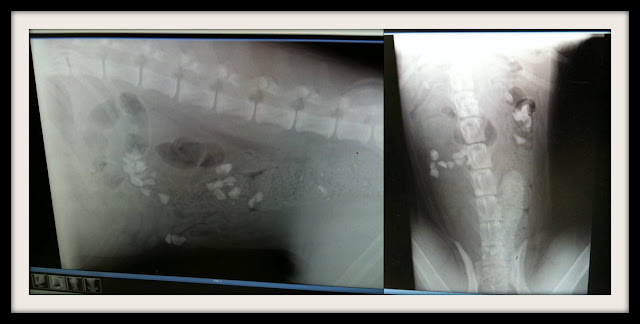

We finished off a dog run we were in the process of building paying for during the summer. It was a really great design with a small portion set up as a potty complete with underground drains and pea gravel. It was going so well until we were woken up at 2AM to some blood curdling yelps.

All the rocks are now gone (in both his belly and the dog run) except for the few still rattling around in that big old adorable pea brain.